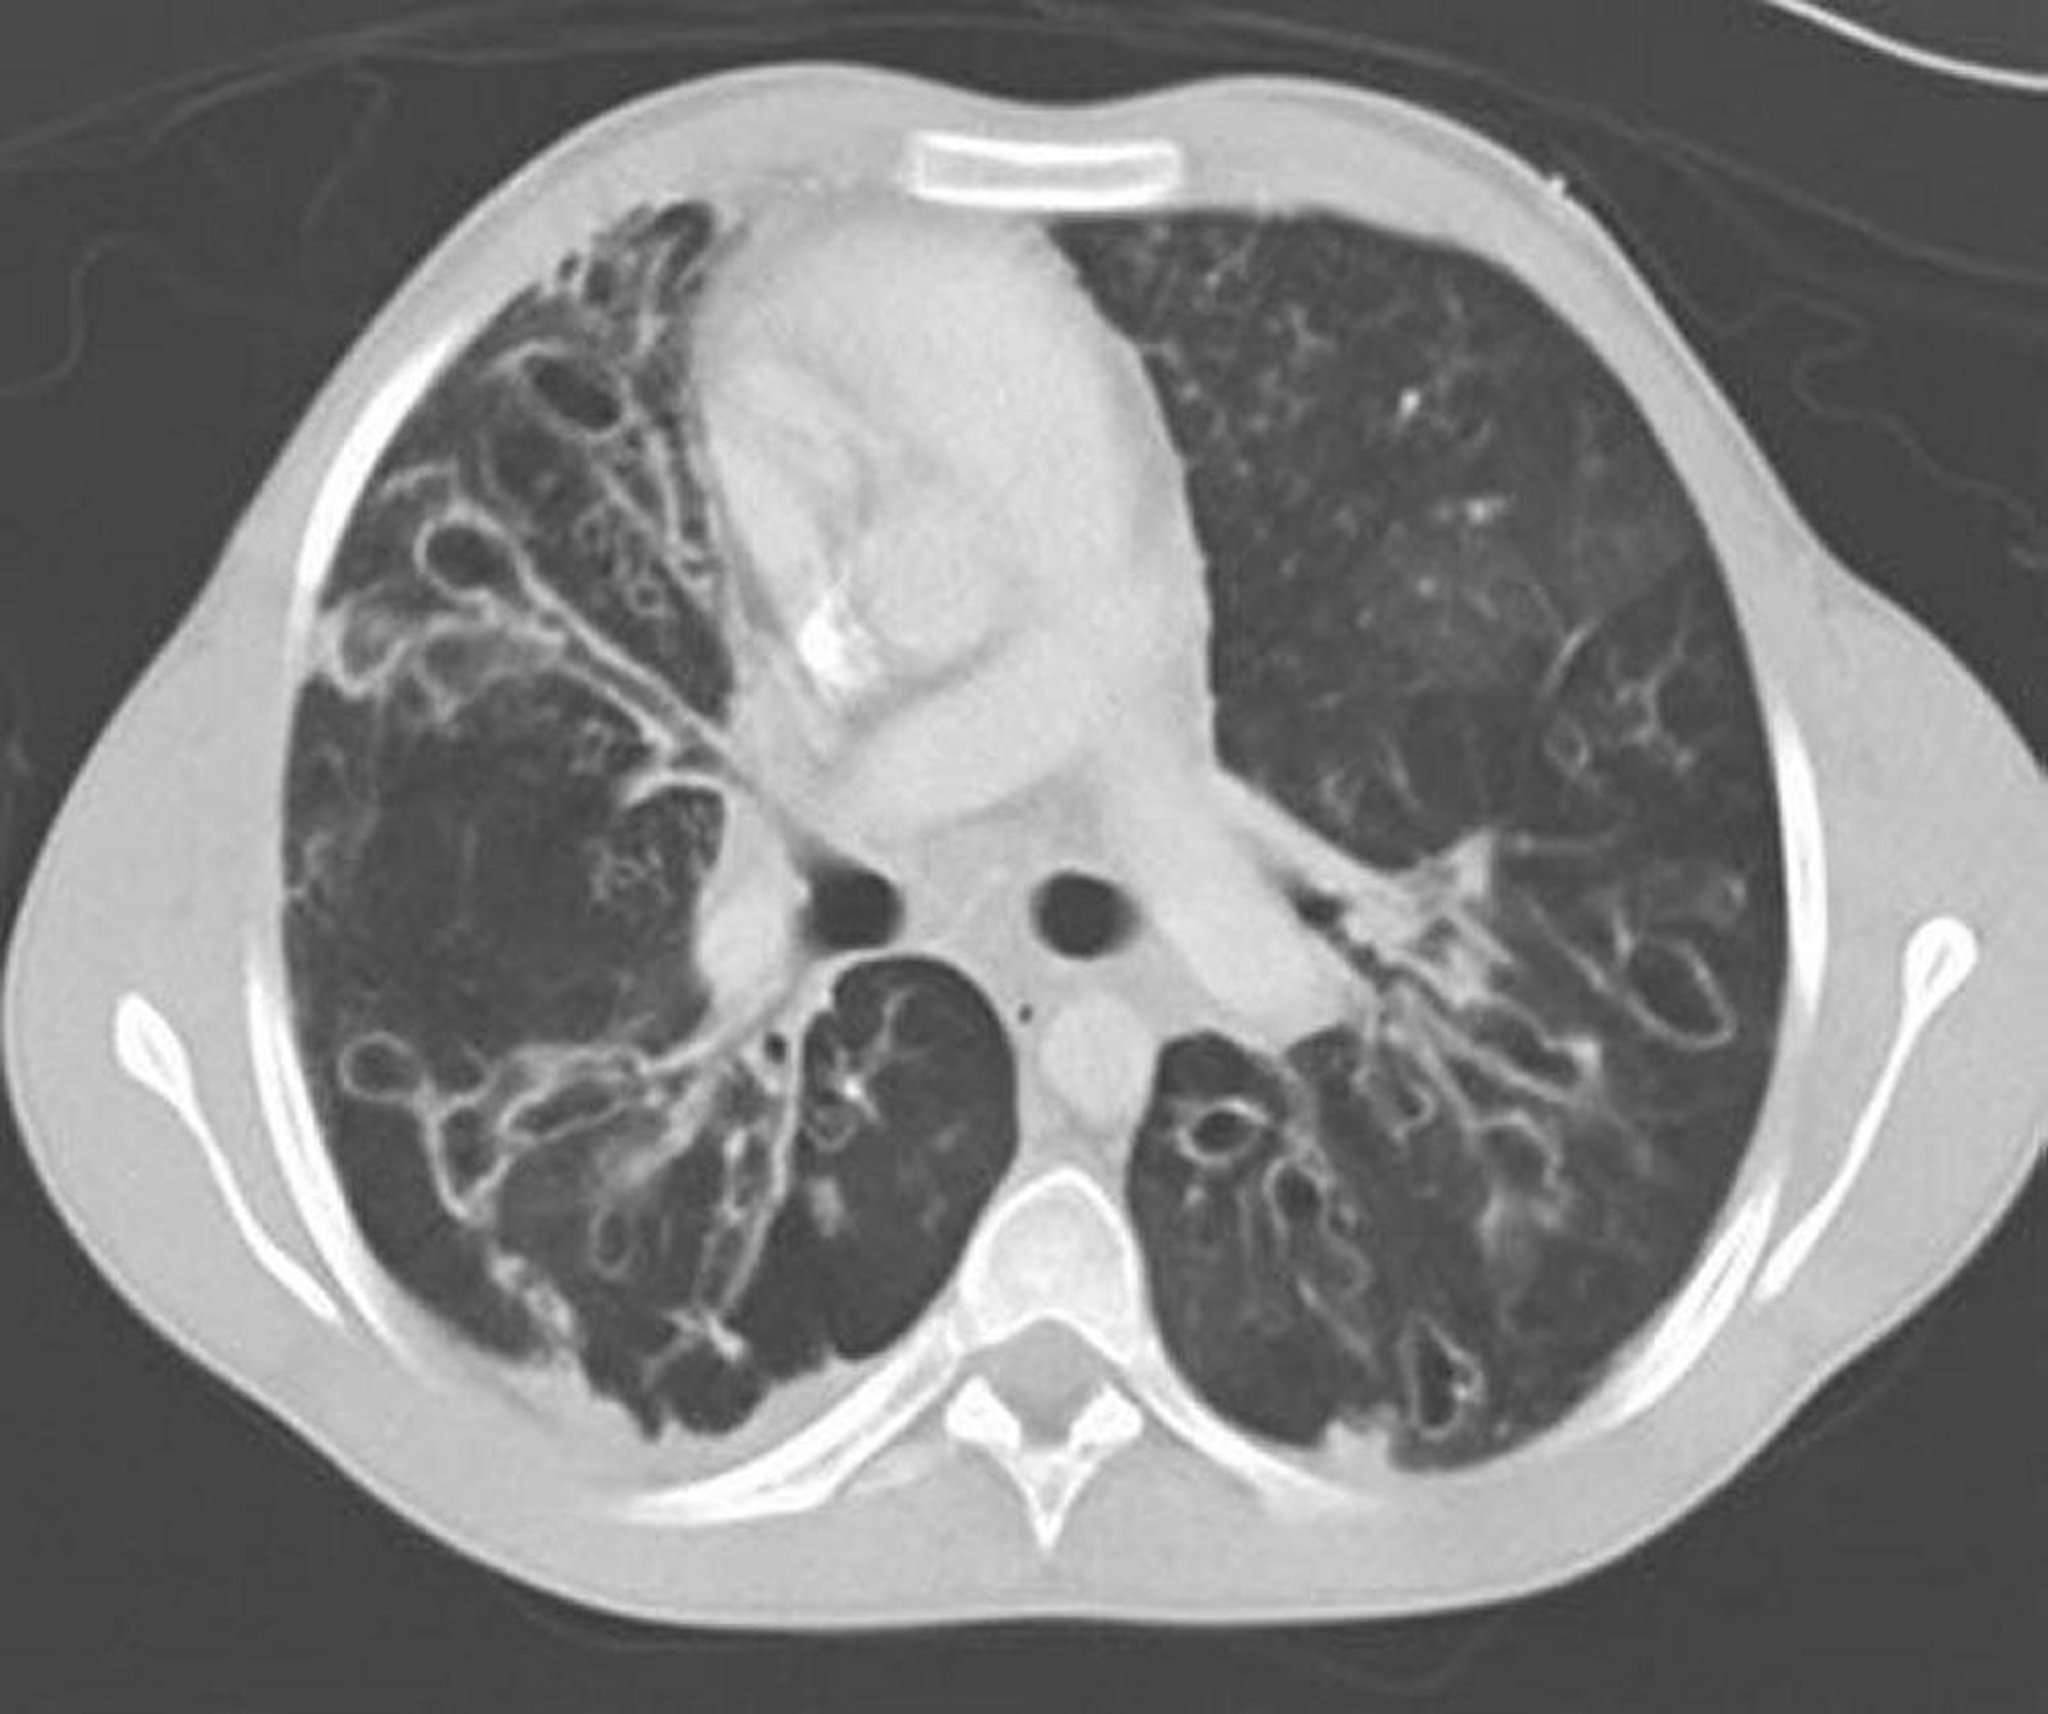

Aspergilose broncopulmonar alérgica (bronquiectasia)

TC de tórax com contraste mostra bronquiectasias graves nas zonas intermediárias do pulmão com vias respiratórias ectáticas e muito dilatadas e alterações císticas. Ectasia das vias respiratórias, caracterizada por uma proporção entre a via respiratória e o vaso adjacente > 1.